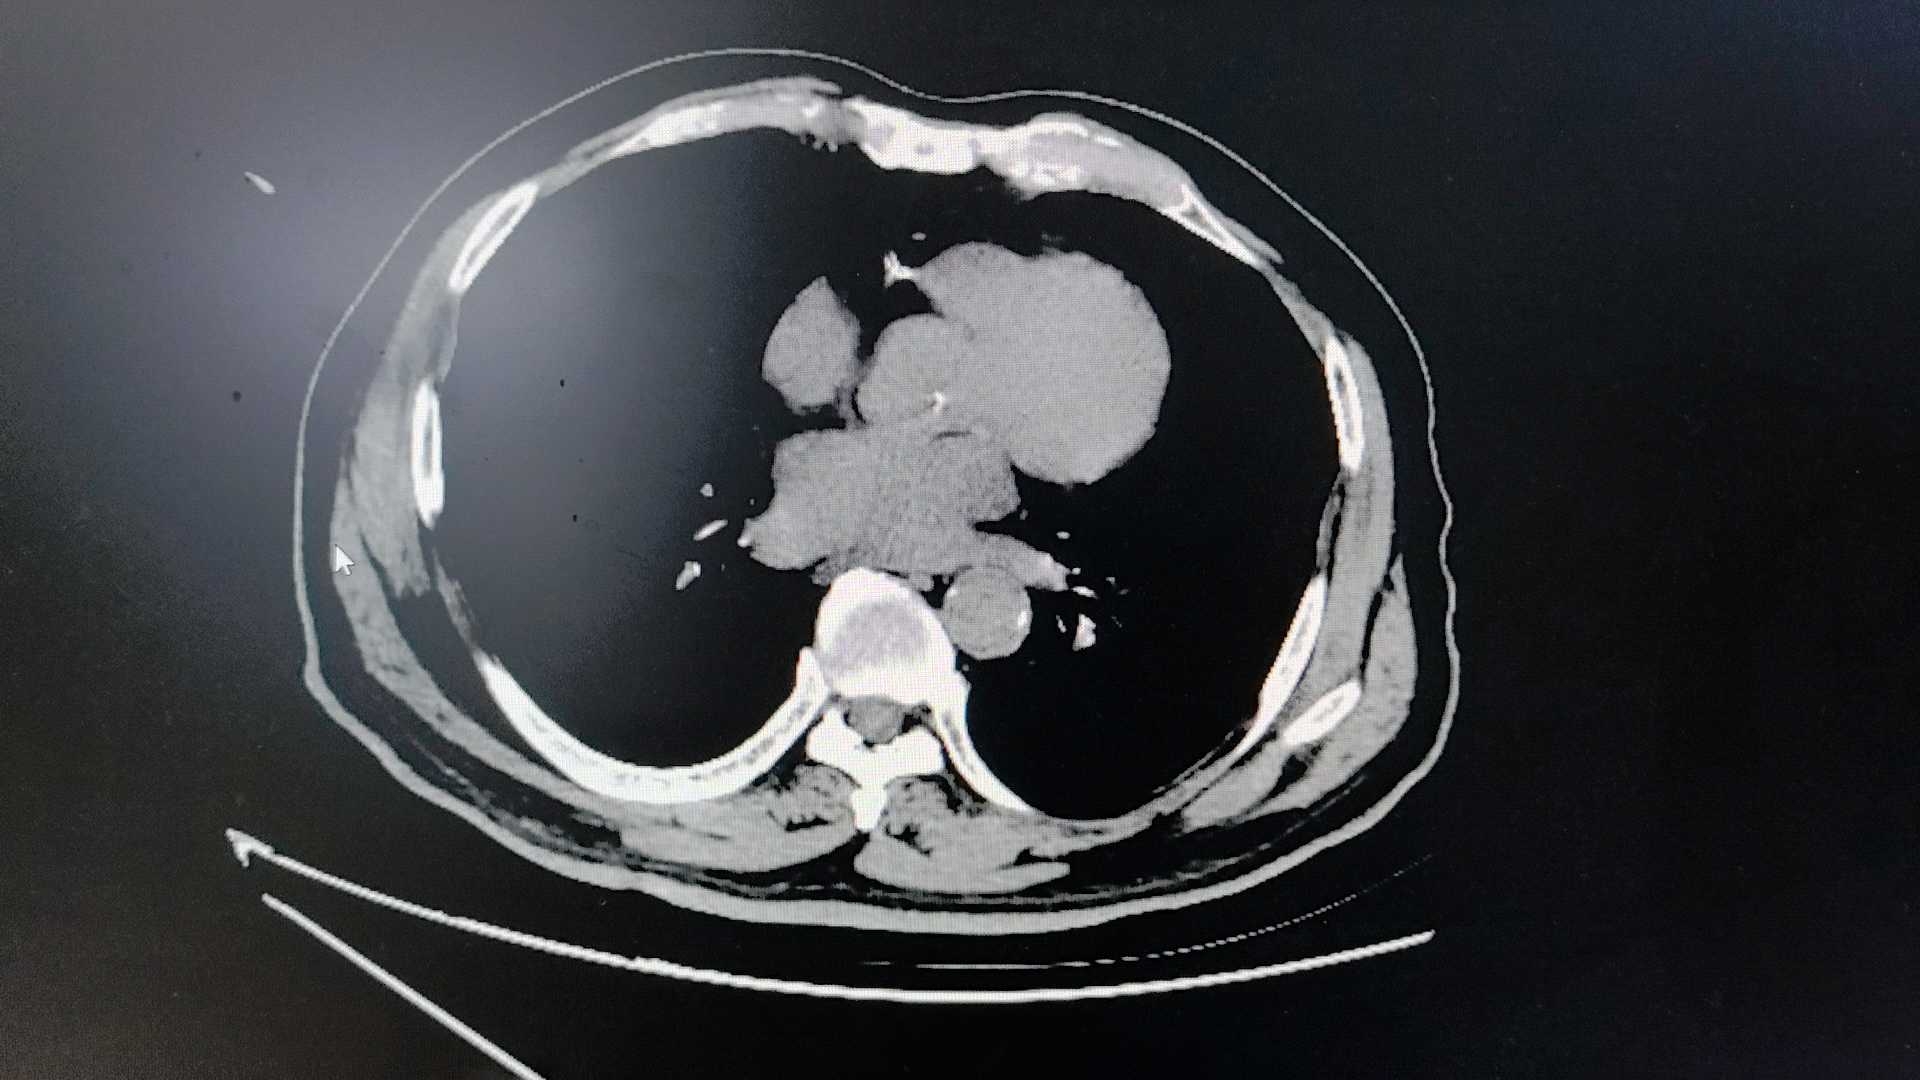

【检查】:入院CT

第二天腹痛加重,复查CT: